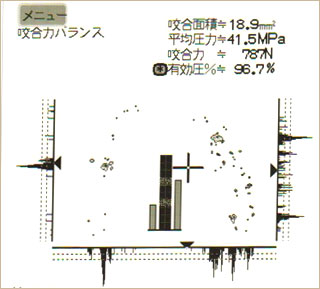

オクルーザーのデータを比較すると、治療前に左の方に偏っていた咬合力が、治療後はバランス良く回復しているのが分かります。